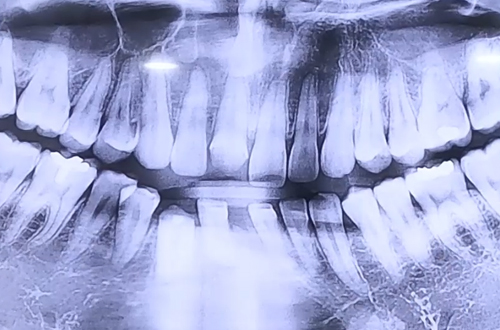

BEFORE

윗니 앞니와 오른쪽 아래 송곳니 보철이 파절된 상태로 내원하신 환자분으로

아랫니 앞니 한 개가 빠진지 오래 되어 주변 치아들이 중간으로 기운 상태이셨습니다.

앞니들 사이는 벌어지고 임플란트 식립할 공간이 좁아져 있었기에

교과서적으로는 치아교정을 하여 공간을 만들어주고 치료를 해야 하는 상황이었는데요.